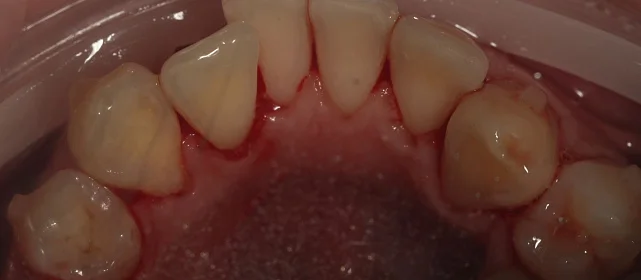

Обратилась с жалобой на скученность верхней и нижней челюсти средней степени тяжести — рецидив после подросткового лечения (ретейнер не носила).

КЛКТ, интраоральное сканирование, пародонтологическое обследование. Подвижности зубов нет, глубина зондирования — в пределах нормы.

Убыль кости — начальная, не превышает 1/4 длины корня.

Дополнительно

рецессия десны в области нижних резцов, старые композитные пломбы на боковых зубах.